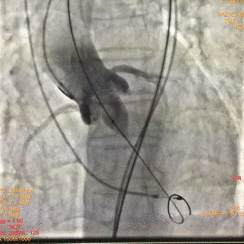

术中影像

图片

根部造影

球囊预扩

瓣膜释放

瓣膜释放完毕

手术结果

术后造影及超声探查未见瓣周漏,跨瓣压差术前56mmHg,术后几乎无压差,术中及术后未出现相关并发症,手术圆满完成。